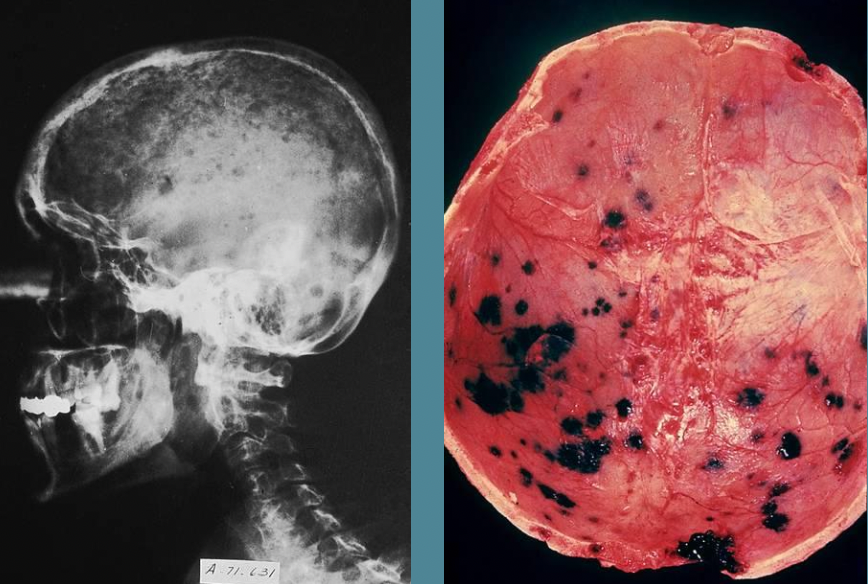

A

Multiple Myeloma with lytic lesions in skull